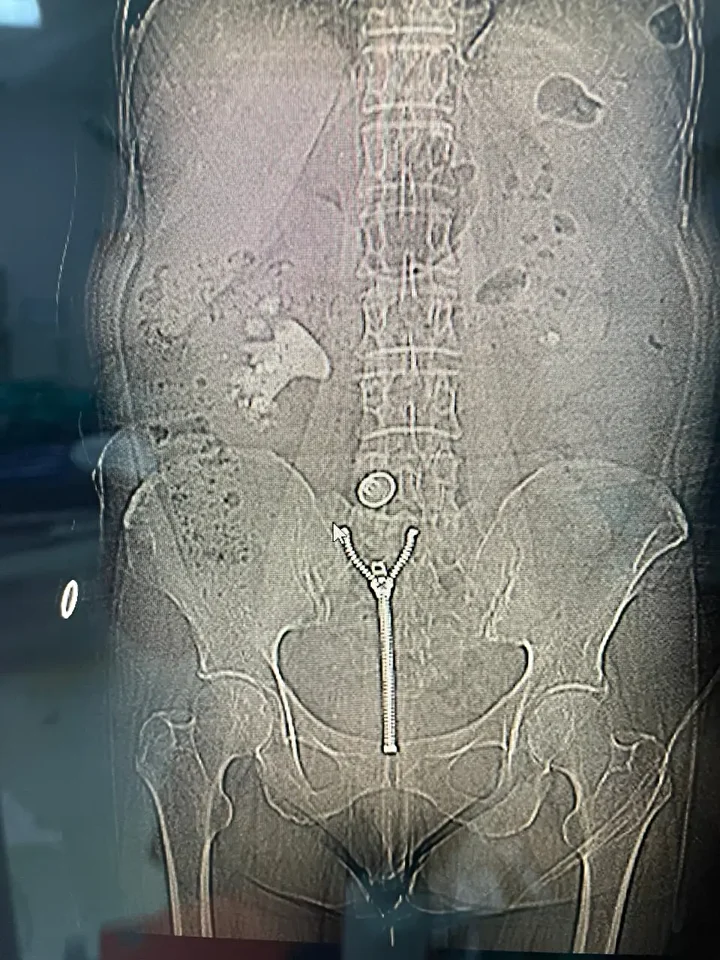

Operasyonu gerçekleştiren Üroloji Kliniği Uzmanı Dr. Mehmet Levent Akbulut, taşın büyüklüğüne dikkat çekerek, "Hastamızın böbreğinde yaklaşık 8 santimetre çapında büyük bir taş vardı. Tıpta bu tabloya ‘staghorn’, yani geyik boynuzu taşı diyoruz. Eğer bu taş alınmasaydı, böbrek fonksiyonunu tamamen kaybedebilirdi. Biz de perkütan nefrolitotomi adını verdiğimiz kapalı yöntemi tercih ettik. Tomografi yardımıyla planlama yaparak, böbreğe küçük bir delikten girip taşı parçalara ayırarak tamamen temizledik. Ameliyat sonrası hastamızın böbreği taşsız hale getirildi" dedi. Dr. Akbulut, söz konusu yöntemin açık ameliyata göre çok daha hızlı iyileşme süreci sağladığını ve bu tür kompleks operasyonların Malatya’da başarıyla gerçekleştirilebildiğini belirtti.

Başarılı operasyon sonrası kısa sürede sağlığına kavuşan Ülkü Sabaner, "Bir akşam şiddetli sancıyla acile başvurdum. Yapılan kontrollerde büyük bir taşım olduğu ortaya çıktı. Doktorlarım kapalı yöntemle ameliyat edilebileceğini söylediler. Pazartesi günü ameliyat oldum, üç gün sonra taburcu oldum. Çıkan taş neredeyse yarım su bardağı kadardı. Açık ameliyata göre çok daha kolay bir süreçti. Bir hafta içinde normal hayatıma geri döndüm. Başta doktorum olmak üzere tüm sağlık çalışanlarına teşekkür ediyorum." ifadelerini kullandı.